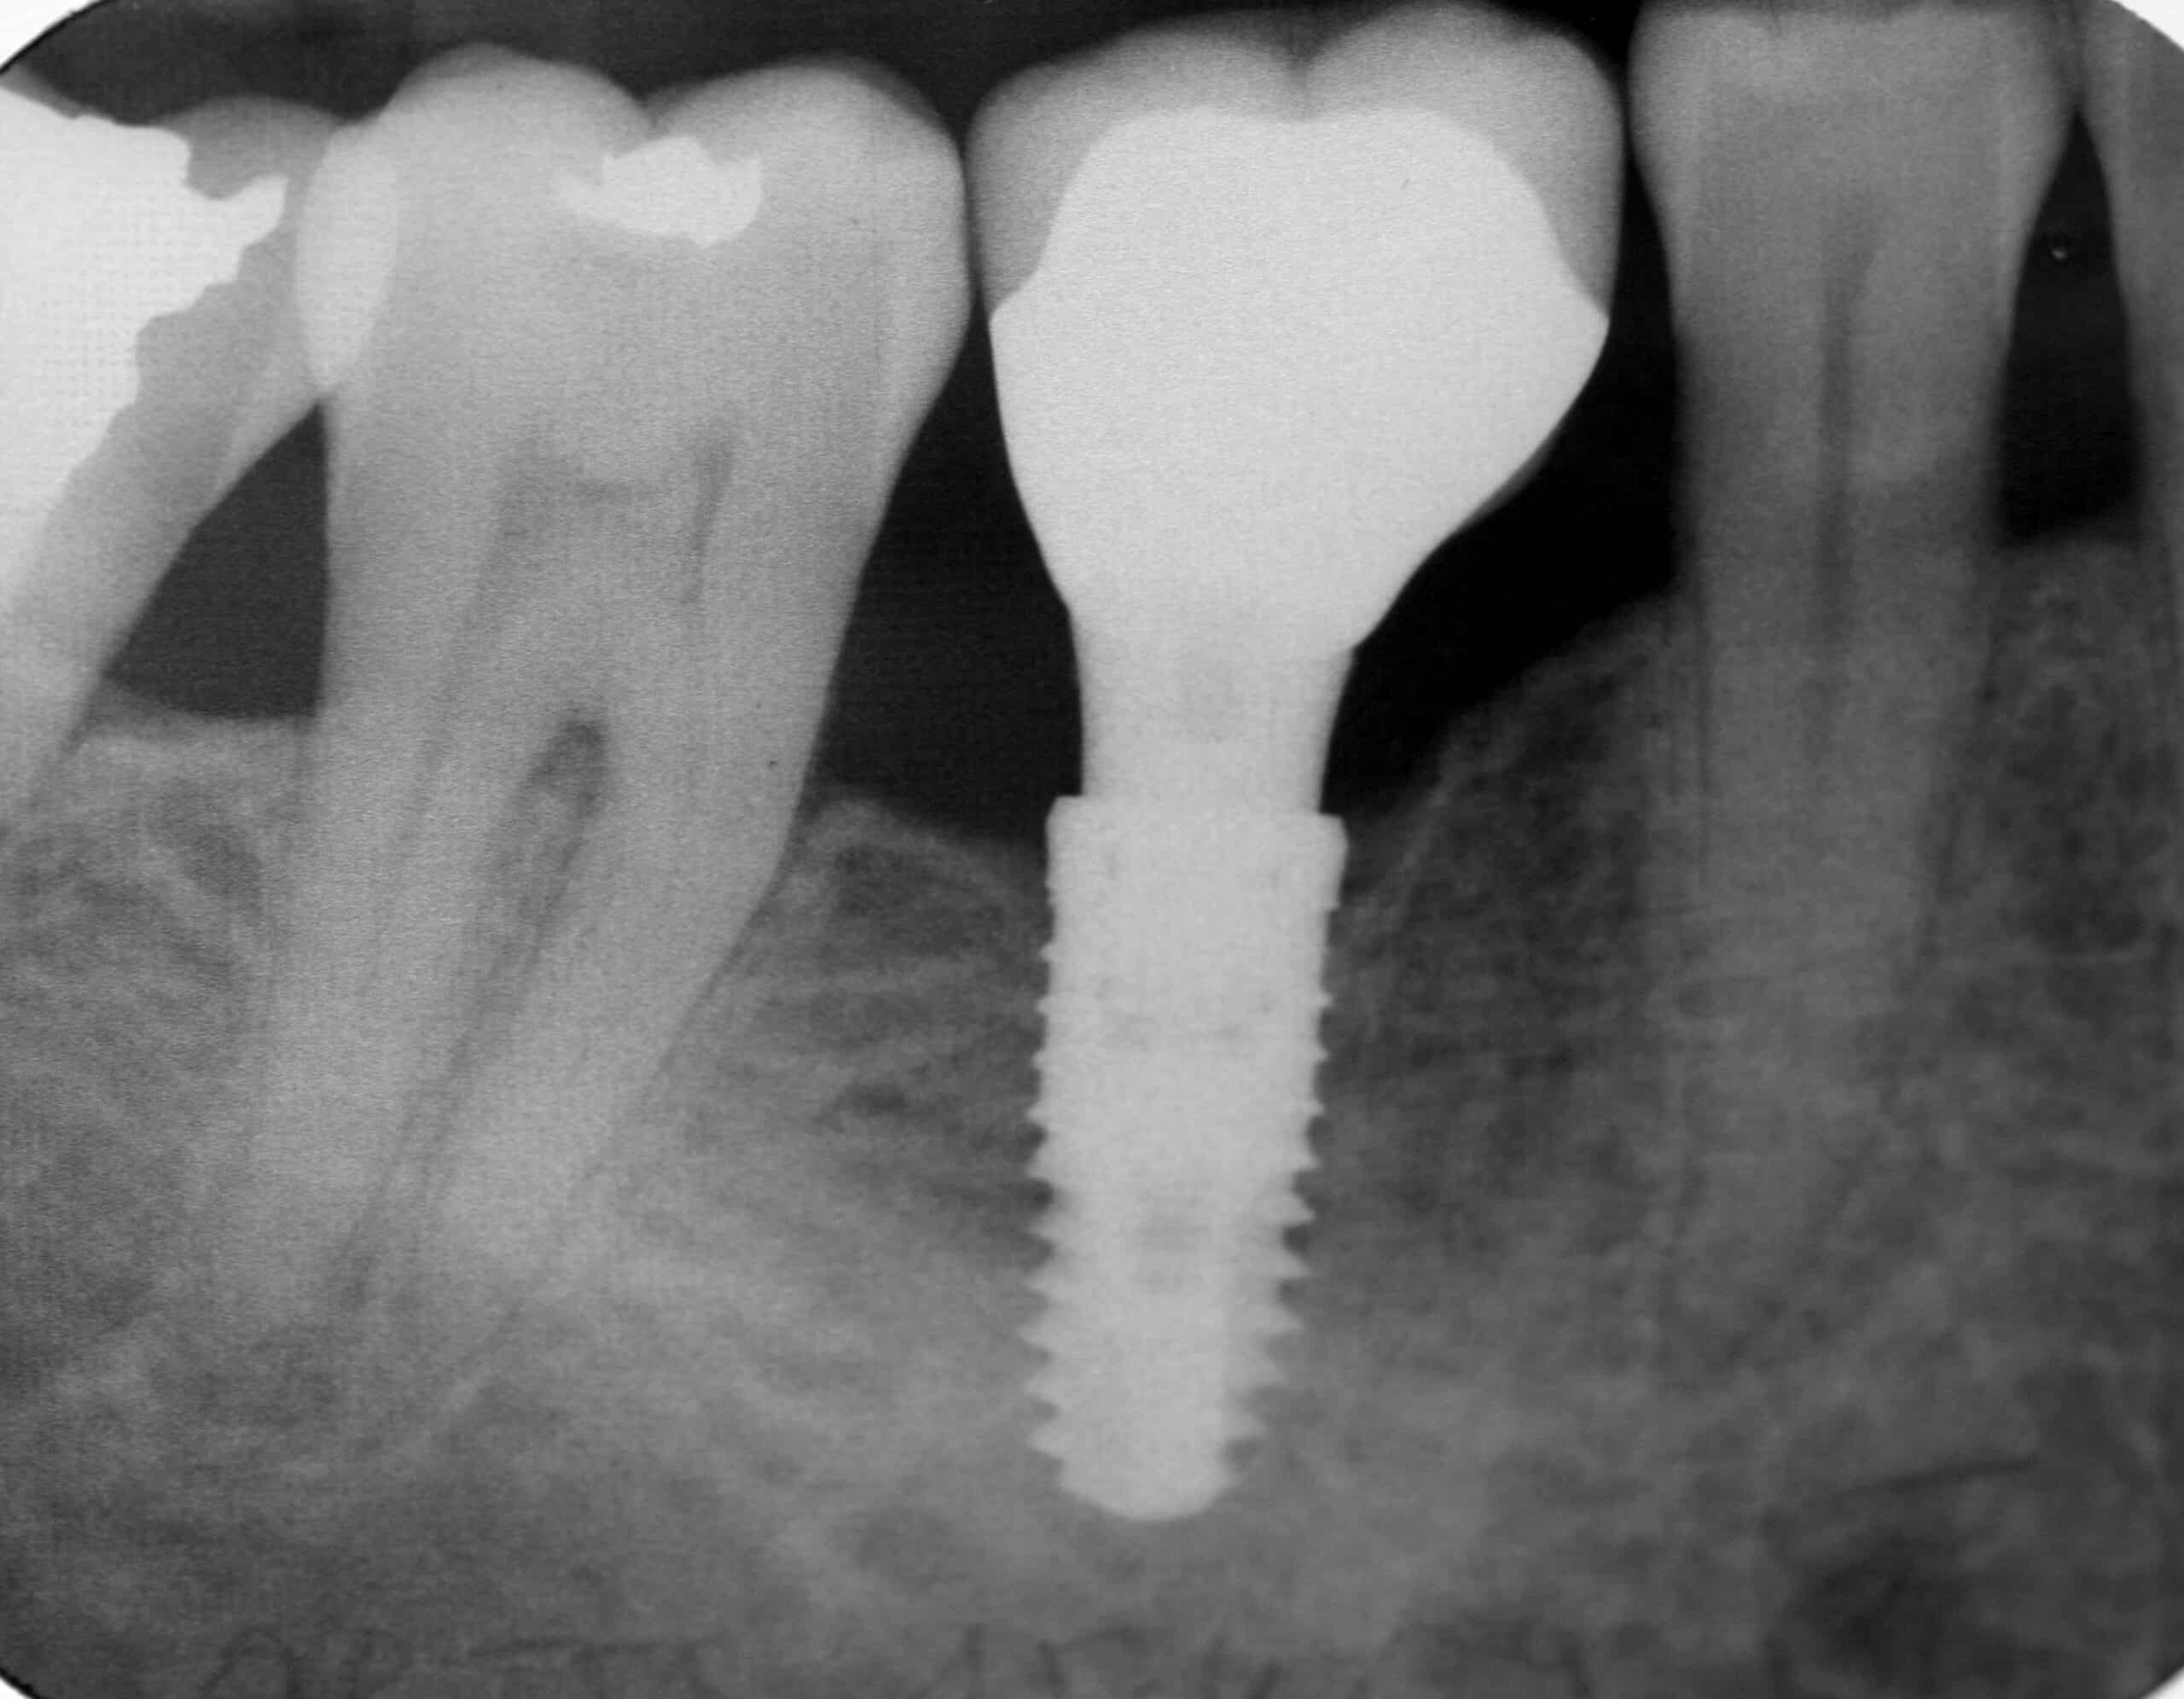

Extraction de dents et implants dentaires lorsqu’il est trop tard

Une carie peut évoluer vers des stades douloureux : atteinte de la dentine puis de la pulpe pour aboutir à l’abcès dentaire. Lorsqu’il est trop tard pour soigner la dent, il faut procéder à son extraction. La dent absente peut alors être remplacée par une prothèse sur implant.

Le prix d’un implant dentaire est libre. Il est donc conseillé de consulter plusieurs spécialistes qui vous fourniront chacun un devis d’implant dentaire.